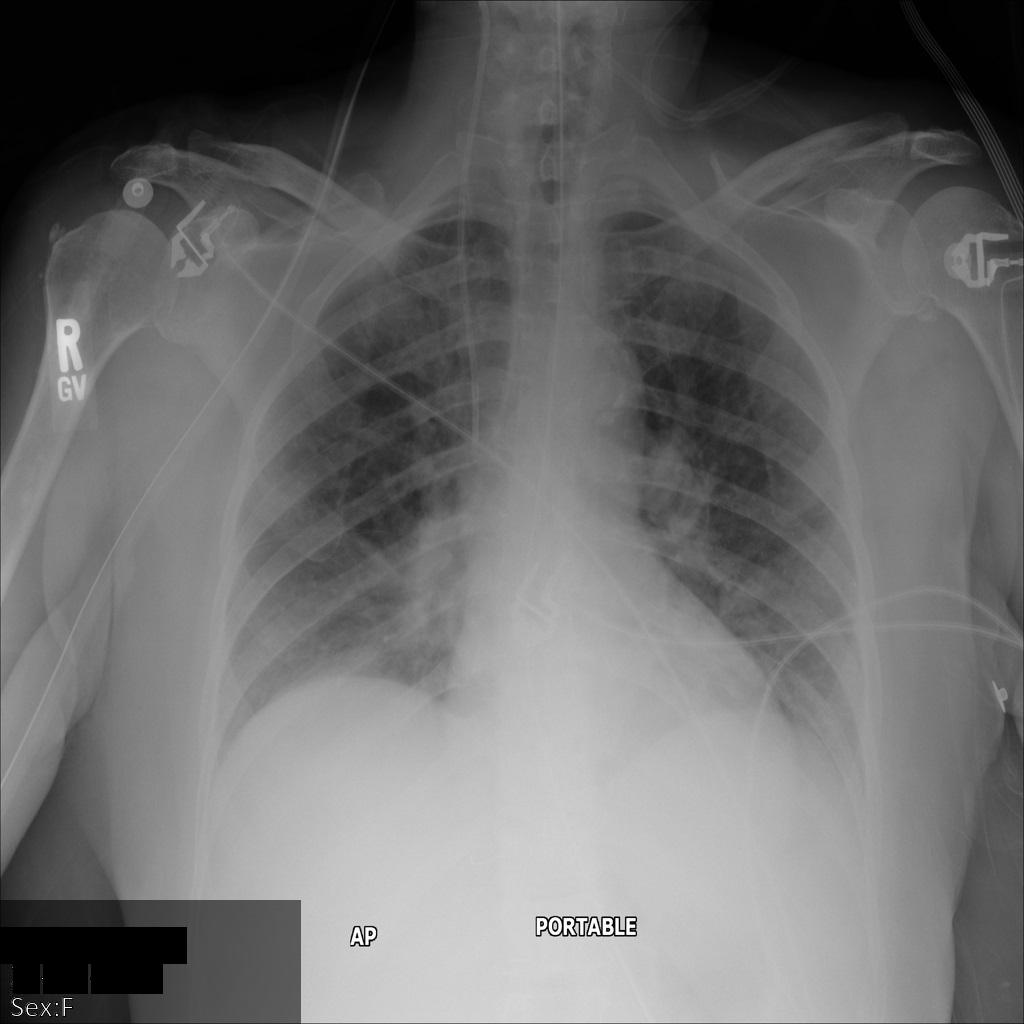

In der folgenden Abbildung sehen Sie eine nicht korrigierte Aufnahme eines Patienten:

Nachdem Sie das Bild mit der Option REDACT_SENSITIVE_TEXT an die Cloud Healthcare API gesendet haben, wird es wie folgt angezeigt:

Folgendes ist aufgetreten:

- Das

PERSON_NAMEunten links im Bild wurde entfernt. - Das

DATEunten links im Bild wurde entfernt.

Das Geschlecht des Patienten wurde nicht entfernt, da dies gemäß den Standard-DICOM-infos nicht als sensibler Text gilt.